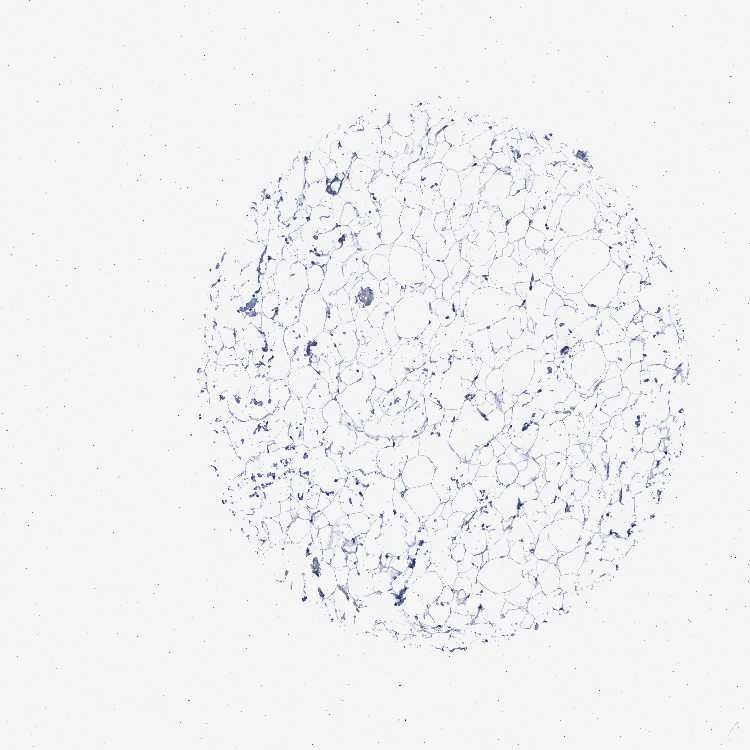

Soft tissuei

On the top, protein expression in current human tissue, based on all annotated cell types, is reported with the units not detected (n), low (l), medium (m) and high (h). Underneath, protein expression in each annotated cell type are reported using the same units.

Protein expression data is based on knowledge-based annotation. For genes where more than one antibody has been used, a collective score is set.

If knowledge-based annotation could not be performed for a gene, no data is displayed here. View antibody staining data further down this page.

Chondrocytes: Not detected

Fibroblasts: Not detected

Peripheral nerve: Not detected